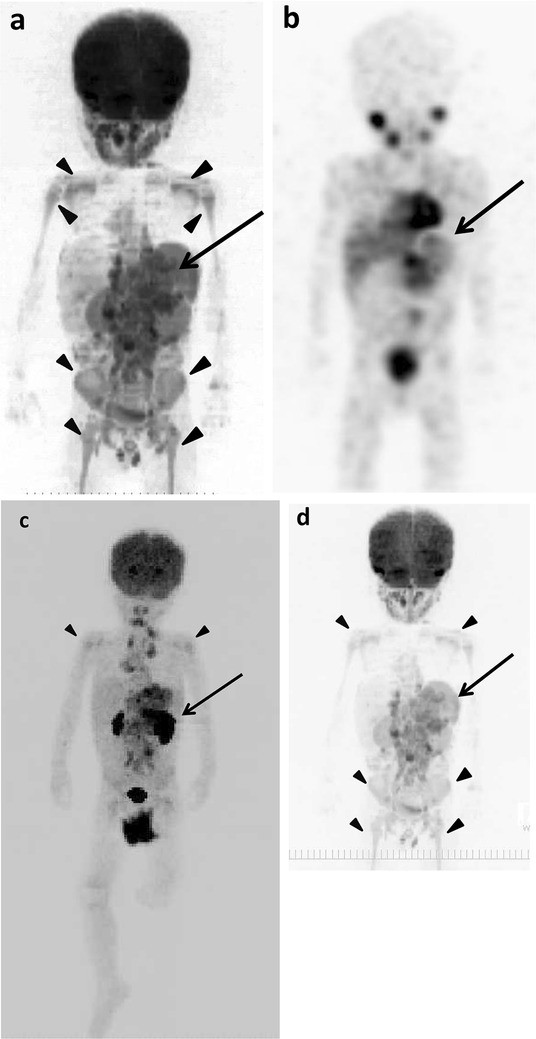

Example images of the original lesions, lymph node and bone metastases, and false-positive findings

The example images of lymph node and bone metastases from neuroblastoma by 18F-FDG PET/CT, DWIBS, 123I-MIBG scintigraphy/SPECT-CT, bone scintigraphy/SPECT, and CT are shown in Figs. 1, 2 and 3. The massive metastatic lesion of temporal bone (Fig, 2a-d) accompanies deformity of bone (Fig. 2e). Diffuse intensive signal of metastasis of lumber spine (Fig. 3a–c, e) does not accompany deformity of bone (Fig. 3d). These findings suggest that bone metastasis involves both cortical bone and marrow.

Fig. 1

figure 1

The original lesions in bilateral retroperitoneal regions, metastases in left supraclavicular lymph nodes, and false-positive images of skeletons of 1 year and 7 months old girl (patient 6). a 18F-FDG PET/CT. b DWIBS. c 123I-MIBG scintigraphy/SPECT-CT. d CT. The maximum intensity projection (MIP) of 18F-FDG PET (e) and DWIBS (f). Long arrows show the original lesions (e, f). Short arrows show metastases (ad). Arrowheads show false-positive images in thoracic spine, left rib and scapula (b) and in various bone segments (e, f)